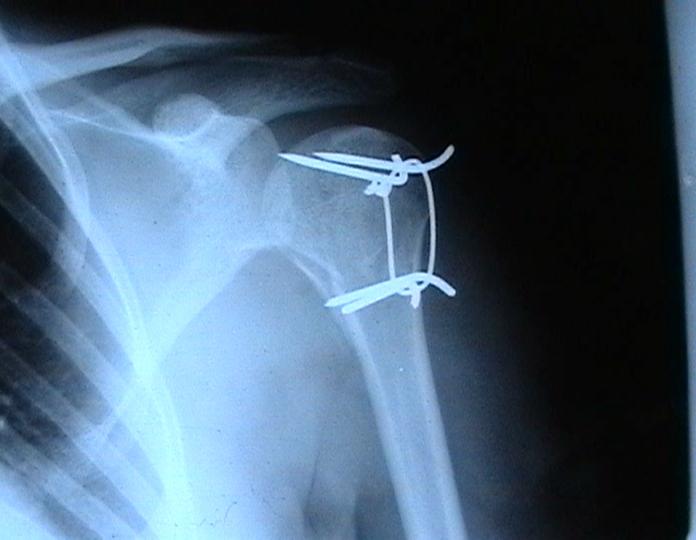

Re: Некроз головки плеча?

Согласен с вашим мнением -асептический некроз головки плеча. Есть ли у вас надежды на реваскуляризацию головки ? Если надеетесь, то имеет смысл продолжать физио, если нет, то следует думать опротезировании.

Переломовывих плеча сложная проблема и технически не уверен как для коллег, но для меня сколько я не встречался, технически сложно *вытянуть* вывихнутую головку из-под впадины. Последнее время не применяю пластины для фиксации перелома, а использую спицы и проволочную петлю (тем более часто и густо спонгиозные винты не держатся в головке прочно).